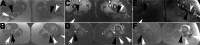

Multifocal desmoid-type fibromatosis (DTF) is very rare and usually regional. We report three cases that initially appeared to be multifocal, but subsequent detailed imaging revealed unsuspected tracking along nerves in two cases. This neural spread is reminiscent of neuromuscular choristoma (NMC), a rare developmental lesion in which mature skeletal muscle cells, or rarely smooth muscle cells, infiltrate and enlarge peripheral nerves. NMC is frequently associated with DTF. These two cases suggest that DTF spread along nerves and appeared as distinct multifocal lesions while actually being contiguous. The third case was felt to represent true multifocal tumor development, possibly due to tumor seeding at the time of chest surgery. The relationship of DTF to NMC is discussed.